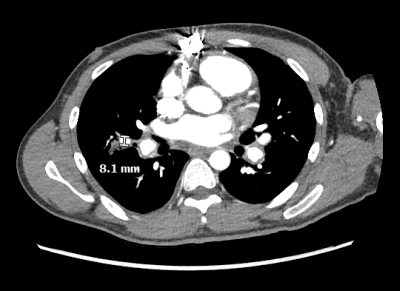

A recently incarcerated 32-year-old man presented with subacute hemoptysis, dyspnea, and night sweats. He had a history of unexplained penile ulcers. His exam was notable for multiple tattoos and a systolic murmur. Chest CTA revealed a 4.6 cm x 2.5 cm right ventricular mass, multiple pulmonary nodules, and bilateral pulmonary emboli. Transesophageal echocardiogram identified a large irregularly bordered mass attached to the anterior tricuspid valve leaflet and right ventricular free wall. Cardiac MRI confirmed a lobulated mass within the right ventricle and an additional 2 cm lesion adjacent to the septum. Multiple sets of blood cultures were negative. Patient had a positive QuantiFERON TB gold and a negative AFB culture, suggesting TB latency. An extensive infectious, hematologic, and rheumatologic workup was otherwise negative. Despite anticoagulation and antibiotics, the mass remained unchanged. The mass was surgically resected, and the tricuspid valve was replaced with a bioprosthetic valve. Histopathology demonstrated an exuberant inflammatory response with organizing granulation tissue from a non-neoplastic process such as organizing hematoma. Postoperatively, the patient developed worsening hemoptysis, requiring intubation and bronchoscopic removal of large airway clots, and upper extremity deep venous thrombosis. Repeat CTA showed multiple pulmonary artery pseudoaneurysms, raising suspicion for vasculitis.

Our patient met the International Criteria for Behcet’s, with a score > 4. Hughes Stovin Syndrome is a rare hypothesized cardiovascular variant of Behcet’s Disease that presents with pulmonary artery aneurysms, venous thrombosis, and intracardiac thrombi. Hematomas on a native cardiac valve in this context have never been reported and may result from similar local endothelial vasculitic processes. Steroids are the mainstay treatment, and anticoagulation is avoided in the presence of pulmonary artery pseudoaneurysms.